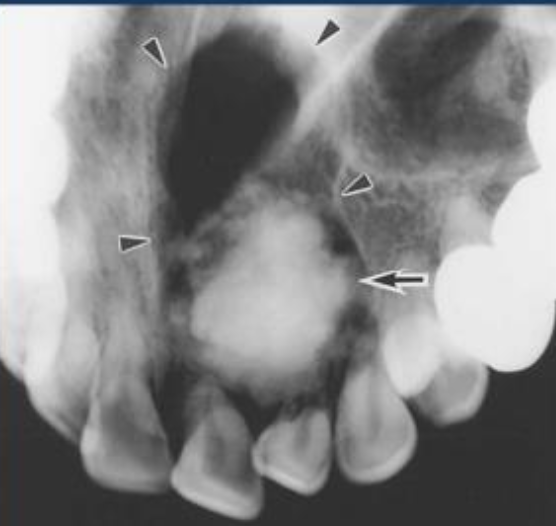

| Odontogenic Keratocyst cyst (OKC) |

|

下顎骨後端,下齒槽管上方 | 10-40y | 組生齒(40%) | |

| Radiolucent、 MD方向下顎骨吸收,但牙根完整。  |

|||||

| 4-8 層、副角化(有核)、Basal cell 為 palisaded(柵狀) | |||||

| 高復發 (30%) | |||||